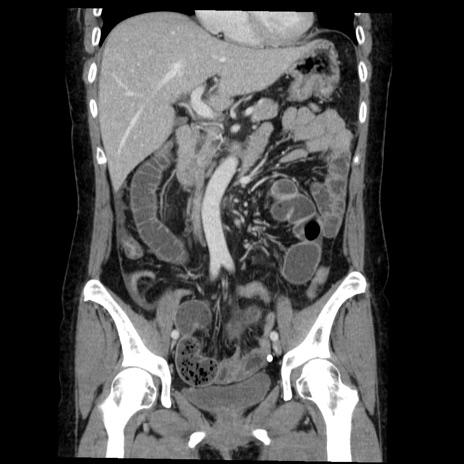

横断像

症例6(冠状断像)

【症例】50歳代女性

【既往歴】卵巣癌術後(8年前に当院で卵巣摘出)

【身体所見】 意識清明、腹部:平坦、腸蠕動音→、やや硬、下腹部自発痛・圧痛あり、反跳痛あり、筋性防御なし。